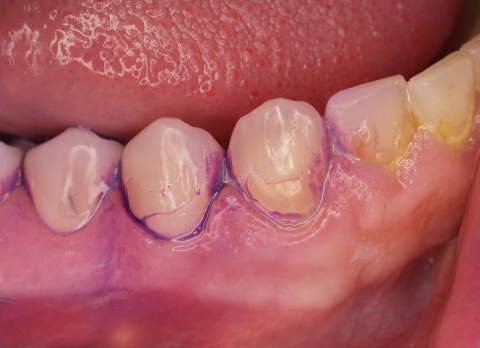

Einsatzvorbereitende Prophylaxe (EVP)

Im Regelfall werden die individualprophylaktischen Maßnahmen im Rahmen einer einsatzvorbereitenden Prophylaxesitzung durchgeführt. Die Besonderheiten des Einsatzes können Auswirkungen auf das individuelle Mundhygieneverhalten der Soldaten/innen haben, sodass die Durchführung der beschriebenen Maßnahmen im zeitlichen Zusammenhang zum bevorstehenden Einsatz sinnvoll ist. In Abhängigkeit von den jeweiligen klinischen Befunden kann die Entfernung harter und weicher Beläge in dieser Sitzung indiziert sein (Abb. 7). Die Entscheidung darüber trifft jeweils der SanOffz/Zahnarzt.